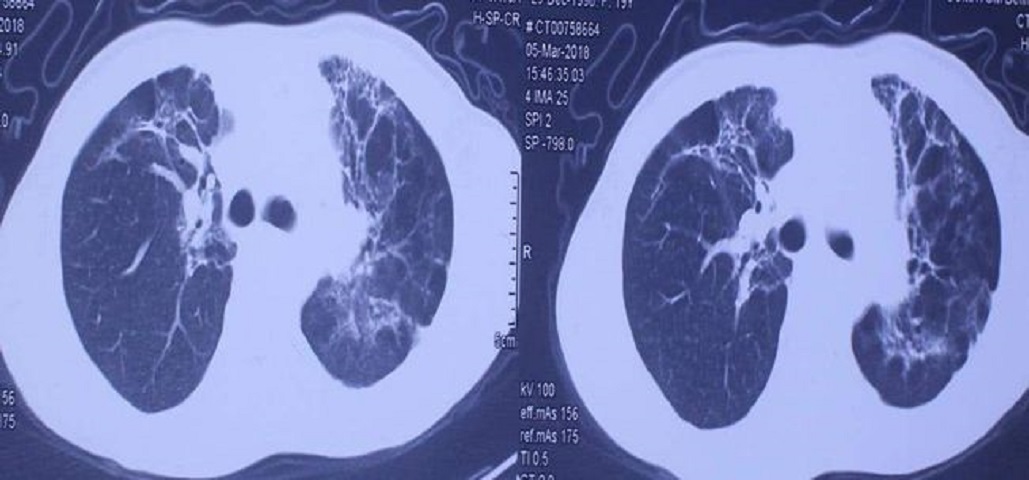

百草枯患者胸部CT

当服用百草枯超过 5毫升 时,百草枯会迅速堆积到肺部,伴随着肺部呼吸的起伏运动将吸收进来的空气,变成 肺泡 ,百草枯再通过肺泡扩散到血液里边,与人体细胞结合,产生强氧化性,并且引起脂质过氧化。

等到反应时间充足,肺泡最先出问题, 肺泡出血、水肿,然后丧失掉原本的所有功能。 没有了肺泡的气体交换功能, 人体的肺部会逐渐纤维化 ,最后会致使整个人体丧失呼吸功能,失去了呼吸功能,人也就死亡了。